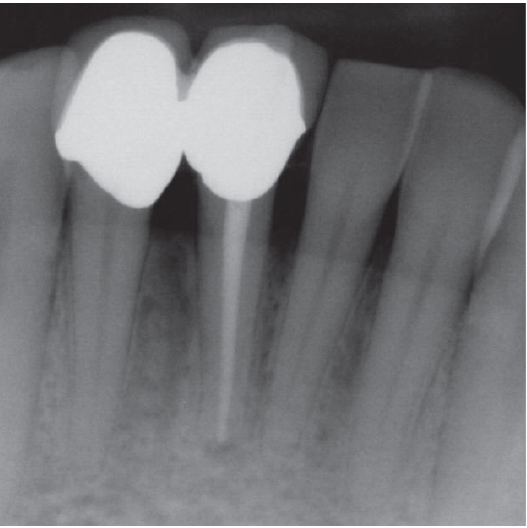

Before

After

Before Root Canal treatment

After Root Canal treatment